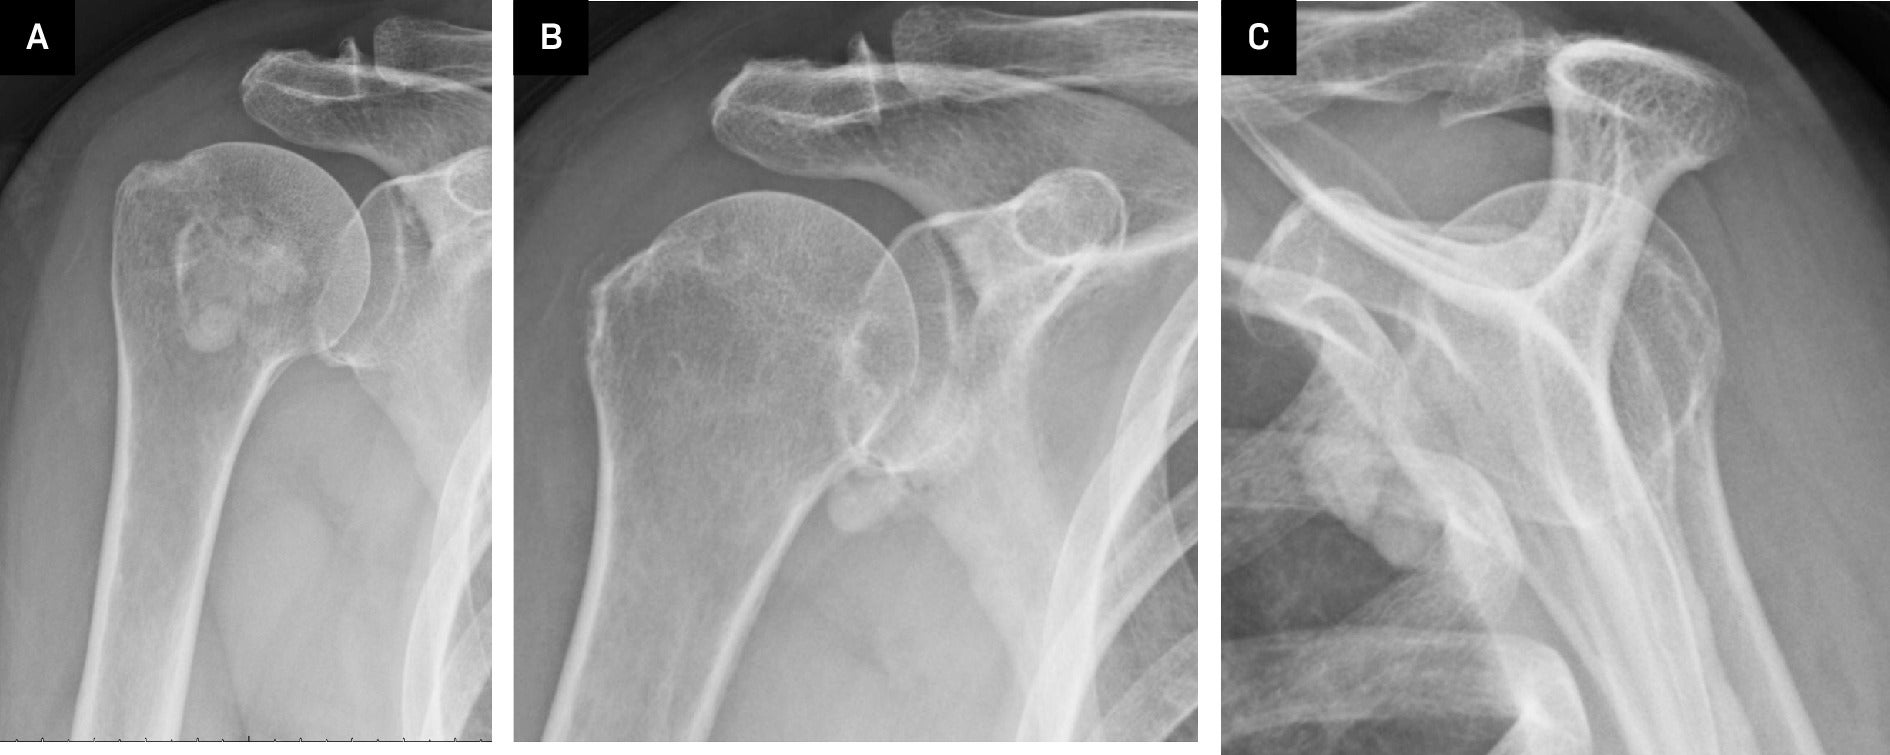

Right shoulder radiographs revealed a 2.8 × 3.4 × 1.7 cm (medial-lateral × craniocaudal × anteroposterior) calcified macro-lobulated density anterior to the humeral head in a subcoracoid position on the scapular Y view ( Figure 1 ). Notably, the calcification appeared denser in the inferior dependent portion. Non-contrast MRI depicted a uniformly mild T2 hyperintense and proton density isointense lesion, relative to skeletal muscle, with layering of hypointense material in the posteroinferior dependent portion, corresponding to the denser calcification observed on radiographs ( Figure 2 ). The lesion resided in a subcoracoid position, anterior to the subscapularis muscle, and extended between the short and long head biceps tendons, within the subcoracoid bursa. These findings were consistent with the location of the multilobulated calcified mass identified on the prior X-ray. Subsequently, an MRI with and without contrast revealed peripheral enhancement around the synovial lining of the distended subcoracoid but no internal enhancement ( Figure 3 ).

Radiographs of the right shoulder: Internal rotation (A), external rotation (B), and scapular Y-view (C) demonstrated multilobulated calcifications adjacent to the glenohumeral joint.